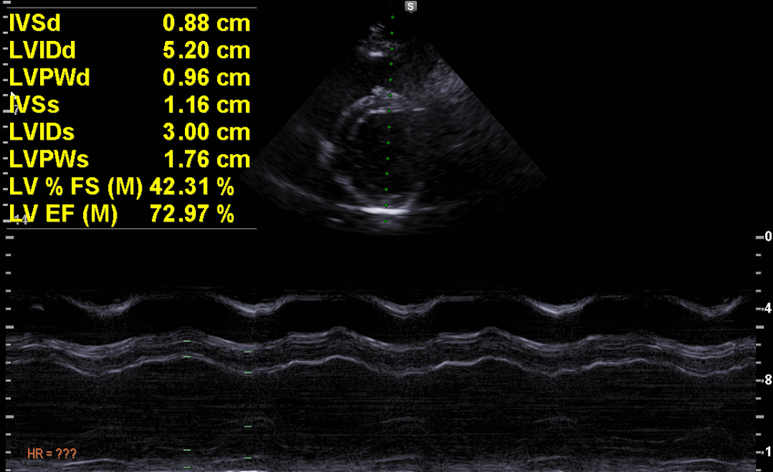

심초음파

M mode에서 수축기 기능은 정상

이완기 기능 특이사항 없음.

경계값에 가까우나 약간의 심비대

경계의 좌심실비대

경도의 이첨판 역류

좌심방 확장 의심